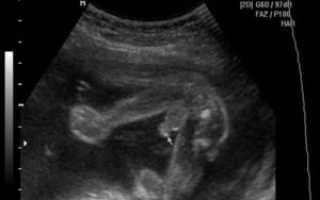

Определить пол ребенка по фото можно в период формирования половых органов. Половой бугорок, расположенный параллельно позвоночнику, свидетельствует о вероятности рождения девочки, а если он расположен под углом 30 градусов, то вероятность рождения мальчика возрастает.

Фотографии УЗИ: На фотографиях УЗИ пол ребенка определяется по характерным признакам. У мальчиков можно увидеть “мужской” орган, а у девочек – отсутствие такового. Однако иногда эти признаки могут быть нечеткими, что приводит к ошибкам в определении пола.

Мы можем определить пол ребенка на 12-й неделе сканирования, оценив направление выступа. Это то, что можно определить у младенцев на этой стадии, и если он направлен вертикально, то, скорее всего, это будет мальчик. Если он направлен горизонтально, то, скорее всего, это будет девочка.